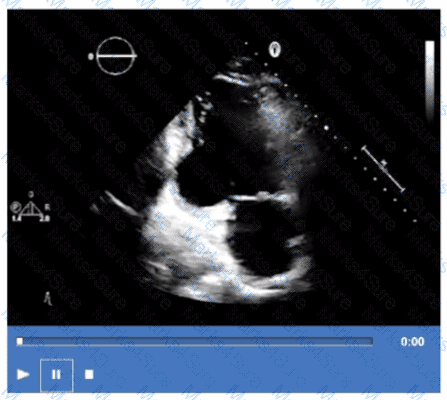

Which coronary artery territory is associated with the wall motion abnormality demonstrated in this video?